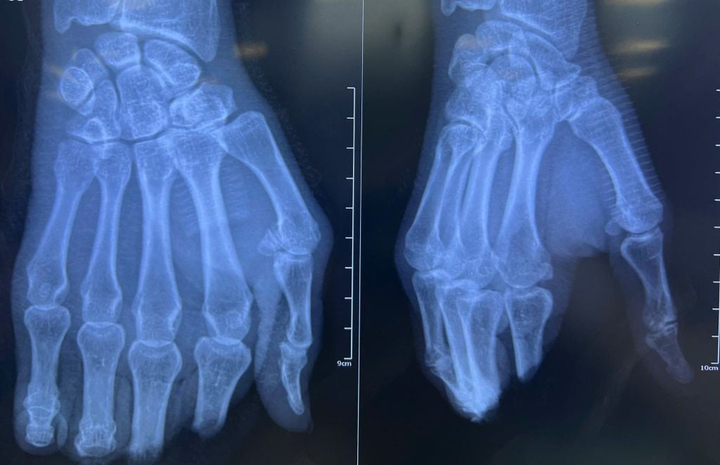

Hình chụp X-Quang bàn tay bị đứt lìa 4 ngón của người bệnh. (Ảnh: BVCC)